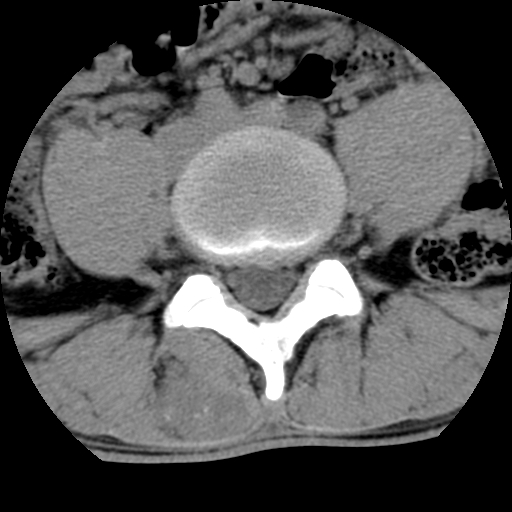

男,腰背痛

本人诊断1tb2包虫,请会诊

1)右侧竖脊肌稍低密度肿块伴钙化(性质待定),不排除肿瘤可能;建议行进一步检查。2)腰椎间盘突出。

1.右侧竖脊肌软组织肿块伴团块状钙化,首先考虑血管瘤可能性大;建议行进一步检查;2。腰椎间盘突出。